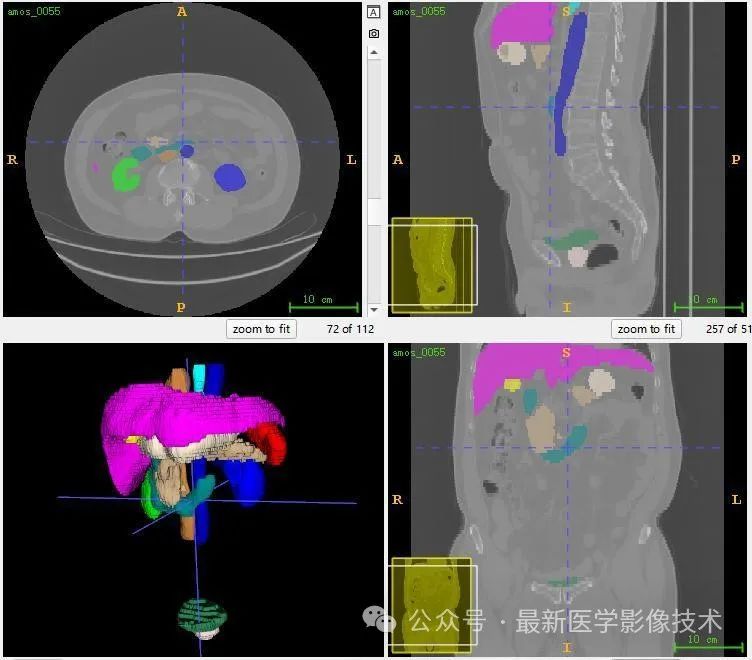

13、测试集分割结果